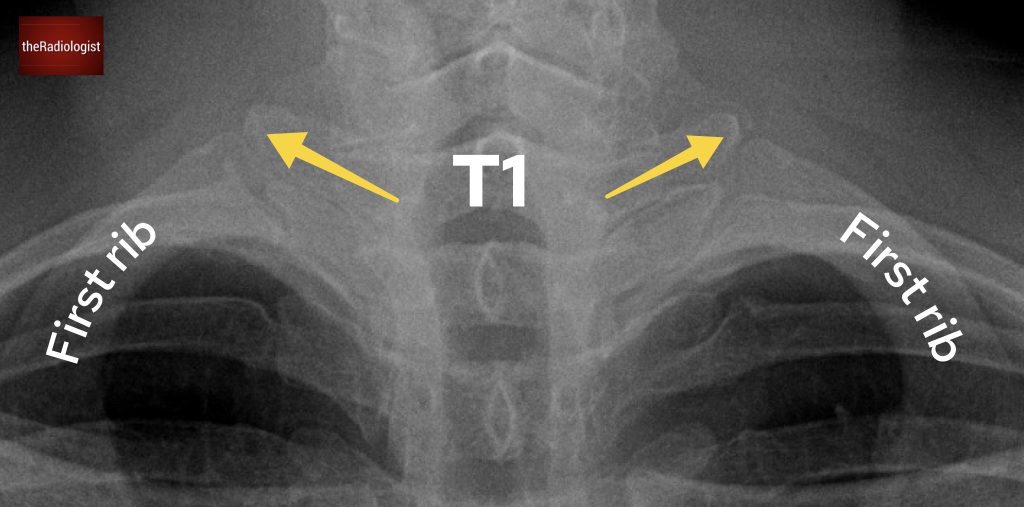

We’ll go back to a PA chest X-Ray for this case. What are the arrows pointing at?

Choose from one of the following options: